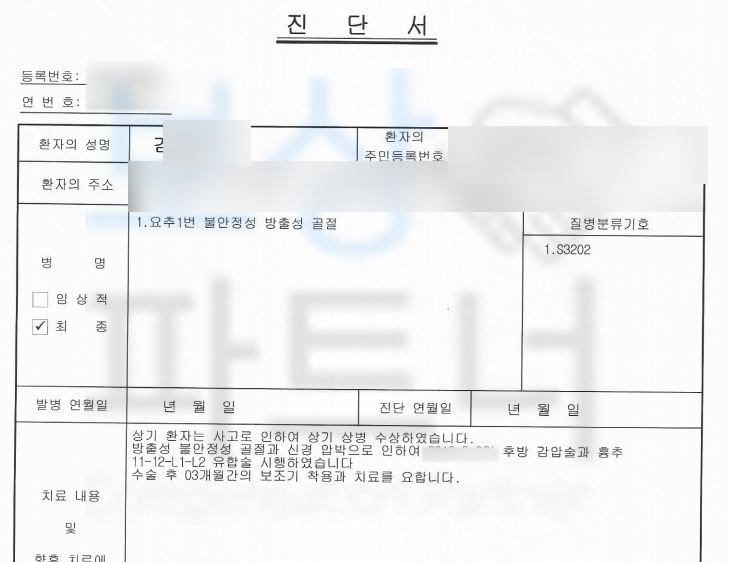

요추 1번 불안정성 방출성 골절 s3202

위 진단으로 신경 손상의 우려가 있기에 **척추 유합술(spinal fusion)**을 받으셨는데요